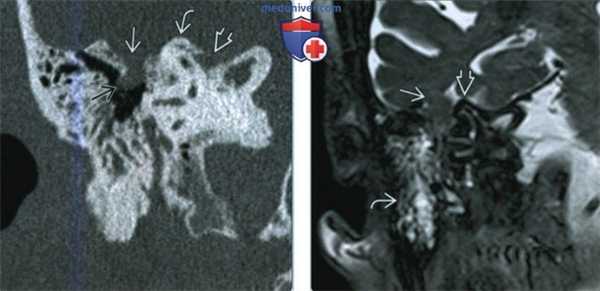

(Слева) При аксиальной КТ в костной окне определяется объемное образование в расширенной ямке коленчатого ганглия с распространением опухоли вдоль переднего барабанного сегмента ЧН VII со смещением слуховых косточек латерально. Наружная поверхность слуховой капсулы истончена ШЛН.

(Справа) При аксиальной МРТ Т1 С+ FS у этого же пациента визуализируется контрастирующаяся ШЛН, расположенная в коленчатом ганглии. Опухоль распространяется вдоль барабанного сегмента ЧН VII и во внутренний слуховой канал по лабиринтному сегменту ЧН VII. Обратите внимание на интрамуральную кисту медиально.